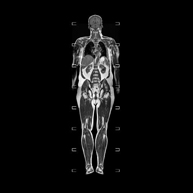

- RM Cuerpo entero (Total body)

Prueba diagnóstica no invasiva que consiste en la obtención de imágenes de alta definición anatómica de todo el cuerpo mediante el empleo de un campo electromagnético y ondas de radio (con un emisor y un receptor). No utiliza radiación ionizante. Es una prueba muy importante en la búsqueda de metástasis en pacientes con neoplasia conocida. No requiere preparación previa. No es necesario el empleo de contraste paramagnético (Gadolinio).